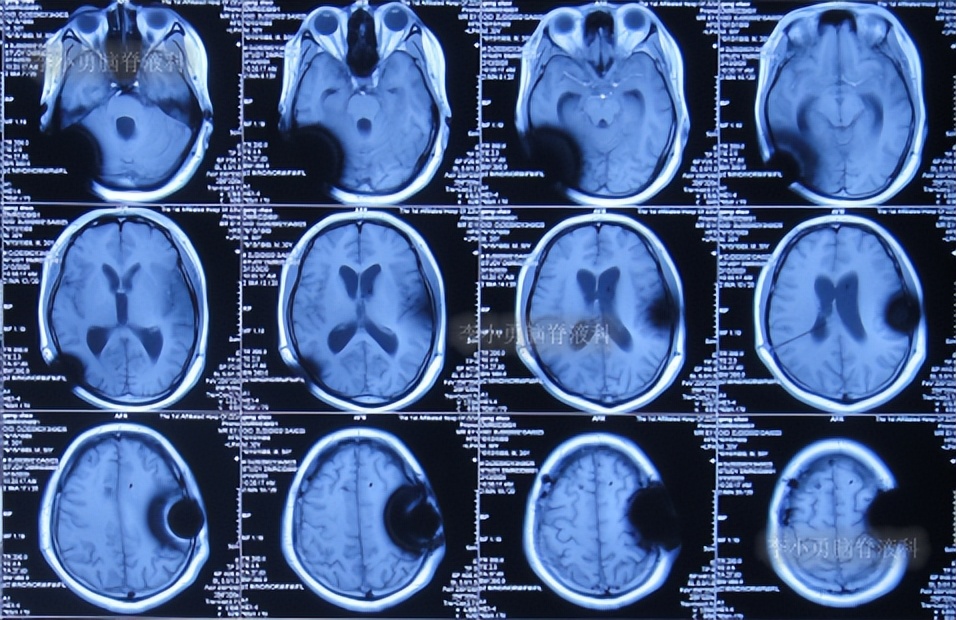

第2次的左侧脑室腹腔分流术后40天即2020年2月9日,查头颅核磁示脑室稍有扩张(图-10)。

图-10:2020年2月9日头颅核磁

第2次的左侧脑室腹腔分流术后44天即2020年2月13日,查头颅核磁示脑室较2020年2月9日有扩张(图-11),未给予特殊处理。

图-11:2020年2月13日头颅核磁